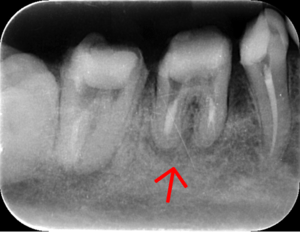

インプラント治療の症例1

レントゲン写真

- 透過像

| 治療方針 | 右下の当該歯は歯根破折により保存不可能と診断しました。歯周疾患も伴っていたため抜歯後に骨吸収※1が大きく起こることが予測できました。チタンメッシュ併用骨再生誘導法(GBR※2)を選択しインプラント埋入と同時に行い自然な歯槽骨のラインを再現しました。またGBRを行う際にインプラント辺縁の付着歯肉の減少が起こる為、遊離歯肉移植術(FGG※3)を行い清掃性を考慮した形態に仕上げました。 ■治療方針の解説 治療した右下の歯をレントゲンで撮影したところ根本の部分に黒く写る箇所があり「根尖性慢性周囲炎※1」と診断。また歯周病も進行していました。 ※1 骨吸収・・・歯槽骨という歯を支える骨がなくなっていくこと |